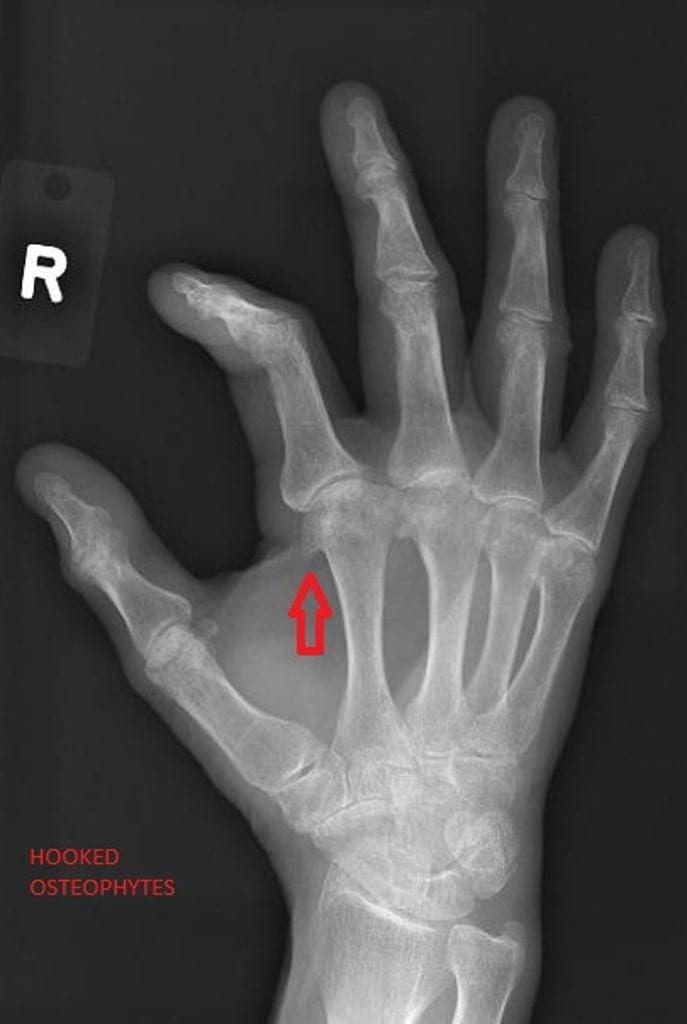

Если лечение полиартрита пальцев рук не осуществляется, то наступает 3 стадия. Пальцы становятся уродливыми, что свидетельствует о сильной степени деформации. Образуются большие узлы и острые остеофиты костей. В некоторых ситуациях они даже могут прорывать покровы кожи.

- Рентгенографическое обследование.